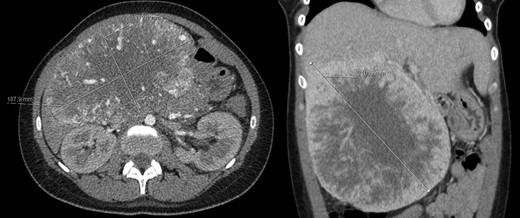

A 40-year-old woman with past medical history of c-section at the age of 26, was referred to our Hepatobiliary Unit in 2013, with diagnose of liver tumor with 16.6 cm (Fig. 2) suggestive of solitary fibrous tumor.

Abdominal Magnetic Resonance – heterogeneous liver mass in segment 4 with 16.6 cm.